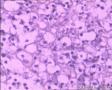

鼻腔新生物

性别年龄80临床诊断

一般病史鼻塞2月

标本名称活检

大体所见小组织三块

恶性肿瘤,IHC分类,首选恶黑、淋巴瘤。

恶性肿瘤,楼上的意见不错,不标记很难分的清,因为肿瘤分化方向不是很显著。

首先考虑恶性淋巴瘤,待IHC吧